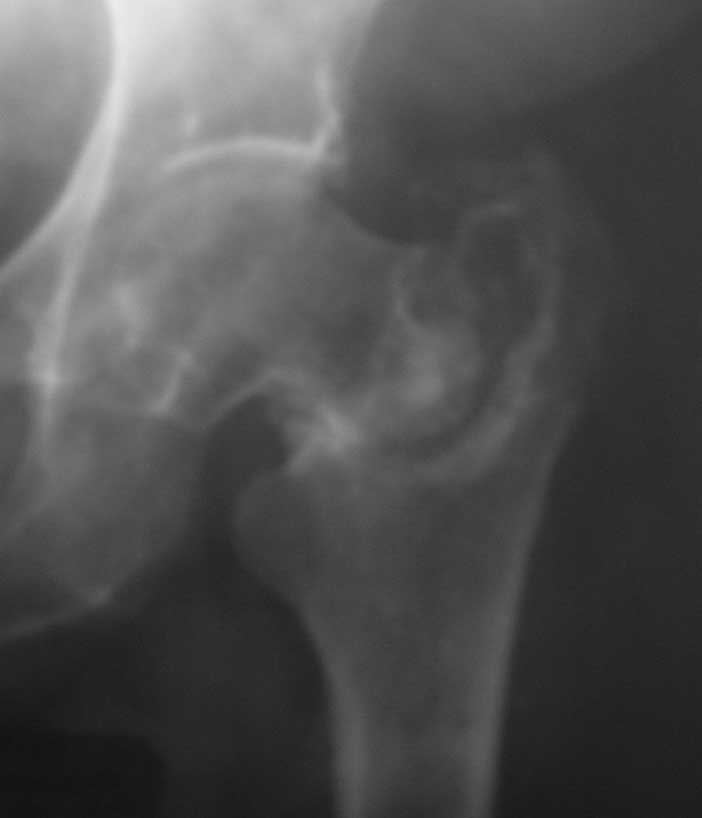

Ложный сустав базальной части шейки бедра |

Больная 61 год. Травма 1 год назад – закрытый базальный перелом бедренной кости без смещения.

Перелом рентгенологически был диагностирован только через 6 недель (на первичных снимках не визуализировался, КТ не проводилось, повторную травму отрицает). Проведен курс консервативного лечения (ходьба на костылях без опоры на левую ногу до 4-х месяцев, ЛФК, физиолечение и т.п.).

В настоящее время передвигается при помощи костылей с незначительной опорой на левую ногу. Больная страдает сахарным диабетом.

Возможные варианты лечения: 1) Тотальное эндопротезирование.

2) Ревизия ложного сустава, возможно костная пластика, МОС углообразной пластиной 130, DHS, AFN.